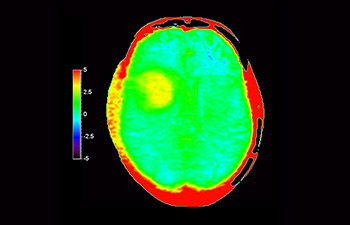

In una società in cui i disturbi neurologici rappresentano un grave problema, Philips si impegna a fornire una efficacia diagnostica senza pari e una guida per il trattamento di tutti i pazienti. Oggi, sebbene la risonanza magnetica sia lo standard di riferimento per l'imaging neuro-oncologico, è comunque possibile migliorarne la precisione nella definizione del grado del tumore e nelle valutazioni di follow-up della terapia. 3D APT (Amide Proton Transfer) è un esclusivo metodo di imaging RM del cervello senza contrasto che permette di ottenere diagnosi più affidabili nel campo della neuro-oncologia. Si avvale della presenza di proteine cellulari endogene per produrre un segnale RM direttamente correlato alla proliferazione delle cellule, un marker dell'attività tumorale. 3D APT è un valido supporto per il personale medico specializzato nella distinzione dei gliomi di grado basso e alto, e nella differenziazione della progressione del tumore rispetto agli effetti della terapia1.

con 3D APT